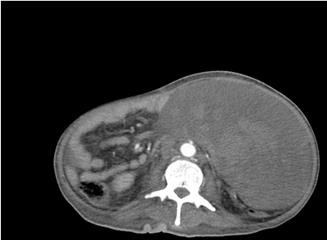

Por consiguiente, se procede a realizar tomografía abdominopélvica axial computarizada con contraste endovenoso, la cual reporta tumoración ovalada retroperitoneal de 19.55 x 10.90, con volumen aproximado de 3300cc con densidades mixtas, que ocupa hemiabdomen izquierdo, sugerida como hematoma retroperitoneal en el reporte oficial del estudio (Fig.1) y (Fig. 2).

Fig.1 Tomografía axial computarizada con contraste abdominopélvica en corte transversal. Muestra masa de densidades mixtas

Los leiomiosarcomas se evidencian como extensas áreas de heterogeneidad y realce heterogéneo, ocasionado por la presencia de necrosis y focos hemorrágicos.

Generalmente no hay presencia de calcificaciones y hay ausencia de tejido adiposo, de esta manera, se puede inferir que una gran masa retroperitoneal mayor a 10 cm sin contenido graso y necrosis interna variable debe sugerir la posibilidad de un leiomiosarcoma. 3,4,10Respecto al caso presentado la evaluación inicial se realizó mediante la realización de un USG Doppler, el cual fue sugestivo de una imagen compatible con hematoma retroperitoneal, lo que llevo a la toma de una tomografía abdominopélvica contrastada, con densidades mixtas, lo cual apoyaba más la impresión diagnóstica de un hematoma retroperitoneal según lo indicado en el reporte oficial.